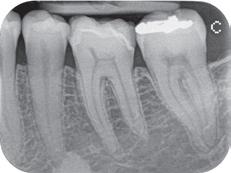

Skriver foto og røntgen i størrelse A6, postkortstørrelse, og gir eksepsjonelle utskrifter. For f.eks. henvisninger, til tanntekniker e.l.

Ypperlig til røntgen!